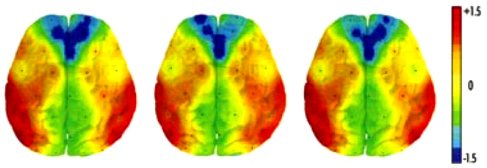

Previous archeoacoustic investigations of prehistoric, megalithic structures have identified acoustic resonances at frequencies of 95–120 Hz, particularly near 110–12 Hz, all representing pitches in the human vocal range. These chambers may have served as centers for social or spiritual events, and the resonances of the chamber cavities might have been intended to support human ritual chanting. We evaluated the possibility that tones at these frequencies might specifically affect regional brain activity. In a pilot project, 30 healthy adults listened to tones at 90, 100, 110, 120, and 130 Hz while brain activity was monitored with electroencephalography (EEG). Activity in the left temporal region was found to be significantly lower at 110 Hz than at other frequencies. Additionally, the pattern of asymmetric activity over the prefrontal cortex shifted from one of higher activity on the left at most frequencies to right-sided dominance at 110 Hz. These findings are compatible with relative deactivation of language centers and a shift in prefrontal activity that may be related to emotional processing. These intriguing pilot findings suggest that the acoustic properties of ancient structures may influence human brain function, and suggest that a wider study of these interactions should be undertaken.